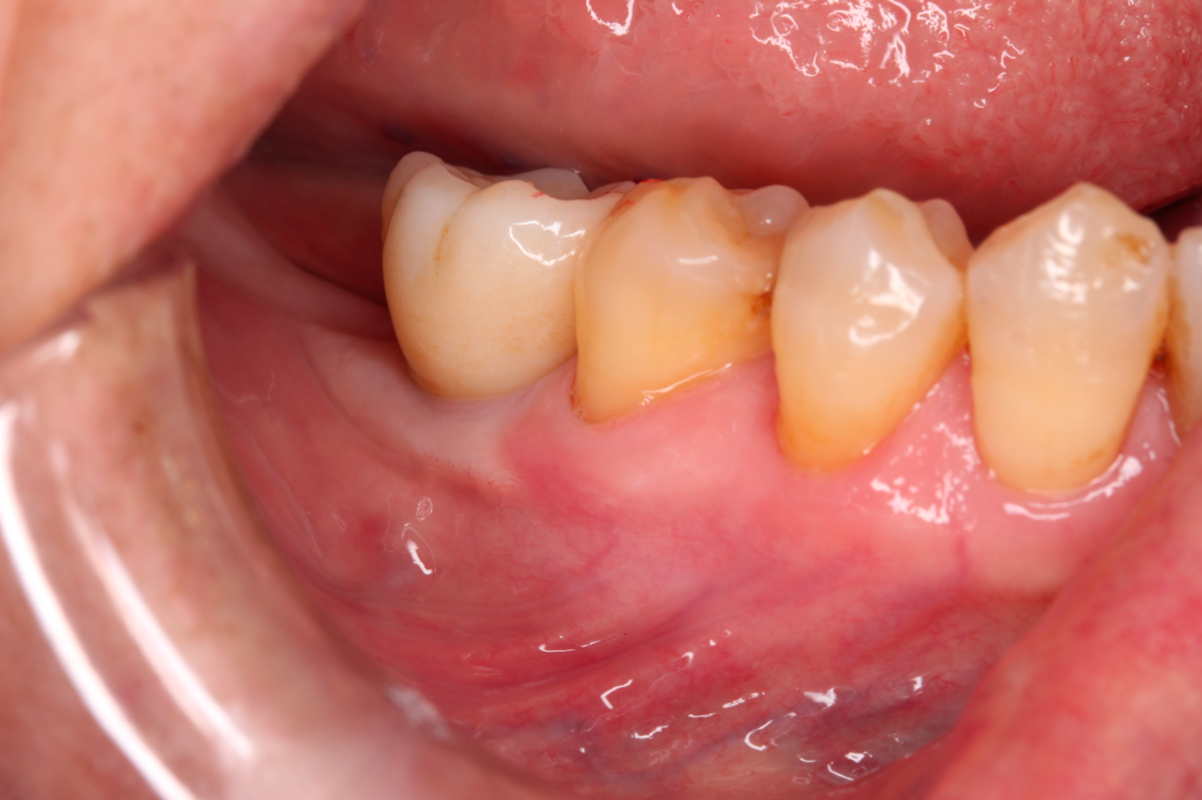

植牙的角化牙齦移植術|提升植牙成功率與美觀性,除了缺牙區,牙肉也要重建!

【治療醫師:林農翔 醫師】   植牙的角化牙齦移植術 植牙的角化牙齦移植術是一種在植牙手術中常見的程序,旨在改善患者缺牙區域的牙齦狀態,提高植牙的成功 …